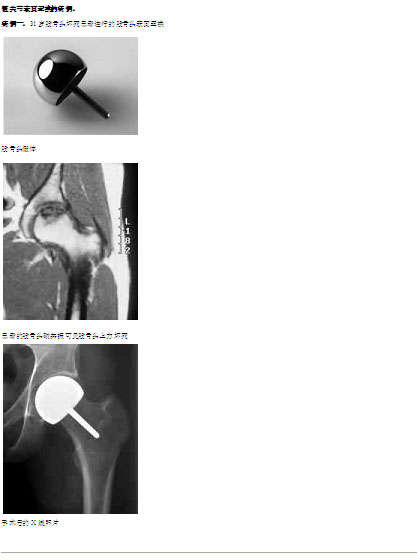

3.年轻病人股骨头坏死,轻度塌陷和囊性变,具有一定的骨质以承担表面假体